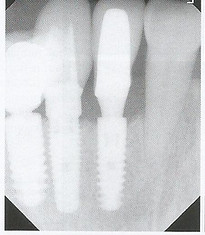

Implant Uncovering

Innovative and unique super-pulsed C02 laser technology, guasian energy distribution and the precise (150 micron) incision width preserves surrounding tissue during implant uncovering and enables immediate impressions with the ideal emergence profile saving you and your patient considerable chair time. Enhance your safety profile as the 10,600nm wavelength is completely reflected off of the implant surface unlike other hot tip lasers.

Periimplantitis Treatment

Rescue failing implants otherwise requiring extraction, bone grafting and replacement by decontaminating the implant surface with the super-pulsed C02 (10,600 nm) laser. It is a safe, effective and effective way to enhance patient care and grow practice revenue. The C02 wavelength can also de-epithelialize the inside of the flap, enhancing the probability of bone regeneration and osetoblast integration into the surface and threads of the implant.